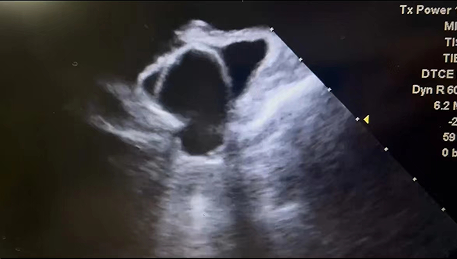

此例手术由韩稳琦博士和酉鹏华博士通过ICE指导下进行,通过ICE精准构建心脏模型、直视下穿刺房间隔,结合三维标测系统,精准、高效地完成双侧肺静脉隔离。后通过ICE及左心耳造影评估左心耳特征为下缘短,上缘折角大的短颈鸡翅型心耳,利用12F导引系统鞘管和猪尾导管在DSA肝位下同时造影,测量左心耳开口25.12mm,最大可用锚定区深度19.71mm,最终选择31mm规格watchman FLX封堵器的植入。ICE从不同角度检查即将释放的WATCHMAN FLX左心耳封堵器,观察封堵器位置、露肩、残余分流和压缩比情况,明确封堵器位置合理,无明显露肩,完全封堵无残余分流,封堵器位置良好。随后在ICE下观察及DSA透视下作牵拉试验,直到最后一次牵拉与前一次牵拉比较无位置改变,压缩比无明显变化,符合封堵器释放的“PASS”原则后完全释放封堵器。

3 术后ICE观察测量Watchman FLX封堵器位置